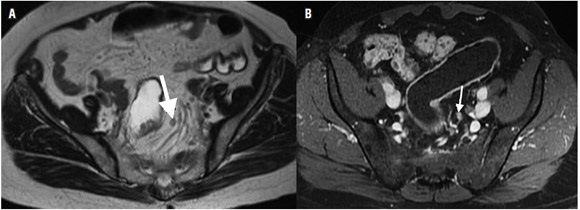

El tamaño de los ganglios linfáticos es un dato de valor limitado para determinar la presencia de metástasis (8,15). Se debe tener en cuenta que hay micrometástasis en ganglios de tamaño normal (5,43,44). Un diámetro de 5 mm tiene una sensibilidad de 68% y una especificidad de 78% para diferenciar ganglios malignos de benignos (8,10,15,45). Este valor no es relevante en el cáncer de recto, ya que entre el 30% al 50% de los ganglios linfáticos con metástasis ocurren en ganglios menores de 5 mm (15,46,47); por lo tanto, la morfología del ganglio linfático, incluyendo los márgenes o contornos y características internas (homogeneidad), son el punto clave para determinar metástasis (8,10,48-51). Un ganglio de aspecto metastásico presenta márgenes espiculados y contenido heterogéneo (15). Las calcificaciones en el interior del ganglio son sugestivas de malignidad (8). A pesar de esto, el problema de basarse en la morfología es que en los ganglios de mayor tamaño no es posible diferenciar entre ganglios neoplásicos o reactivos, y en los ganglios de menor tamaño pueden no identificarse las micrometástasis (figura 7A) (18). Cabe anotar que la sensibilidad de la resonancia magnética reportada en la literatura para la detección de ganglios linfáticos varía entre el 39% al 95% (5-7,22,52,53,54,55).

Se ha usado medio de contraste (gadolinio) para la valoración de los ganglios linfáticos con estudios que reportan una precisión de hasta 70% (figura 7B) (5,8). Heriot y colaboradores reportan una sensibilidad y especificidad superiores al 80% para la detección de compromiso ganglionar cuando se usan antenas intrarrectales (22,56).